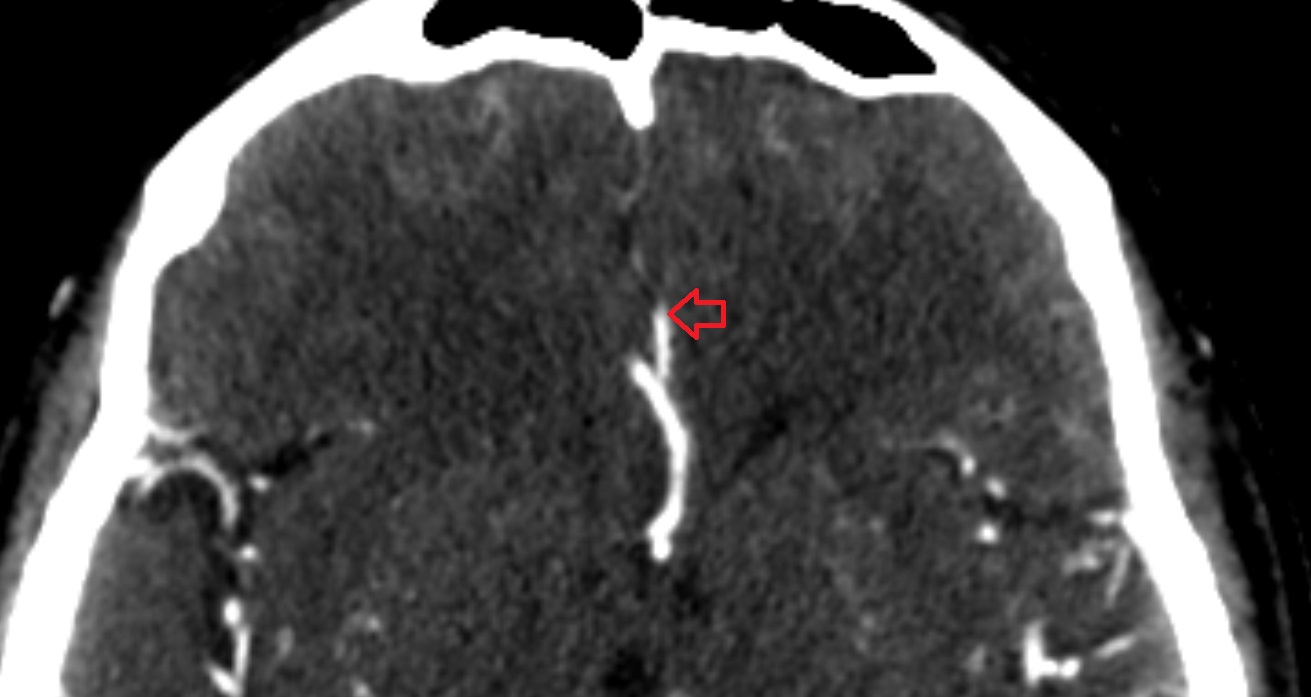

- Middle cerebral artery

- Middle cerebral artery horizontal segment (M1)

- Middle cerebral artery insular segment (M2)

- Middle cerebral artery opercular segment (M3)

- Middle cerebral artery cortical segment (M4)